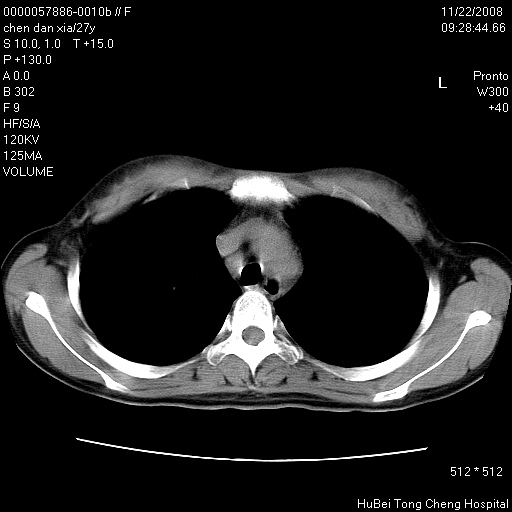

标题: CT16752:F,27Y。发热咳嗽20余天,伴盗汗。 [打印本页]

标题: CT16752:F,27Y。发热咳嗽20余天,伴盗汗。

右下肺见片絮状影,两肺野内分布不均的小结节影,结核并肺内播散可能性大,建议结合实验室检查 .

右下肺纹理模糊;纵隔可见肿大淋巴节;右心缘旁结节,边缘光滑,纵隔窗病变范围较肺窗明显小,首先考虑右下肺结核,不排外淋巴瘤

好像有微结节,建议薄层以除外结核

似有粟米状结节。考虑粟粒型肺结核?

1)考虑两肺感染性病变。2)纵隔淋巴结肿大。